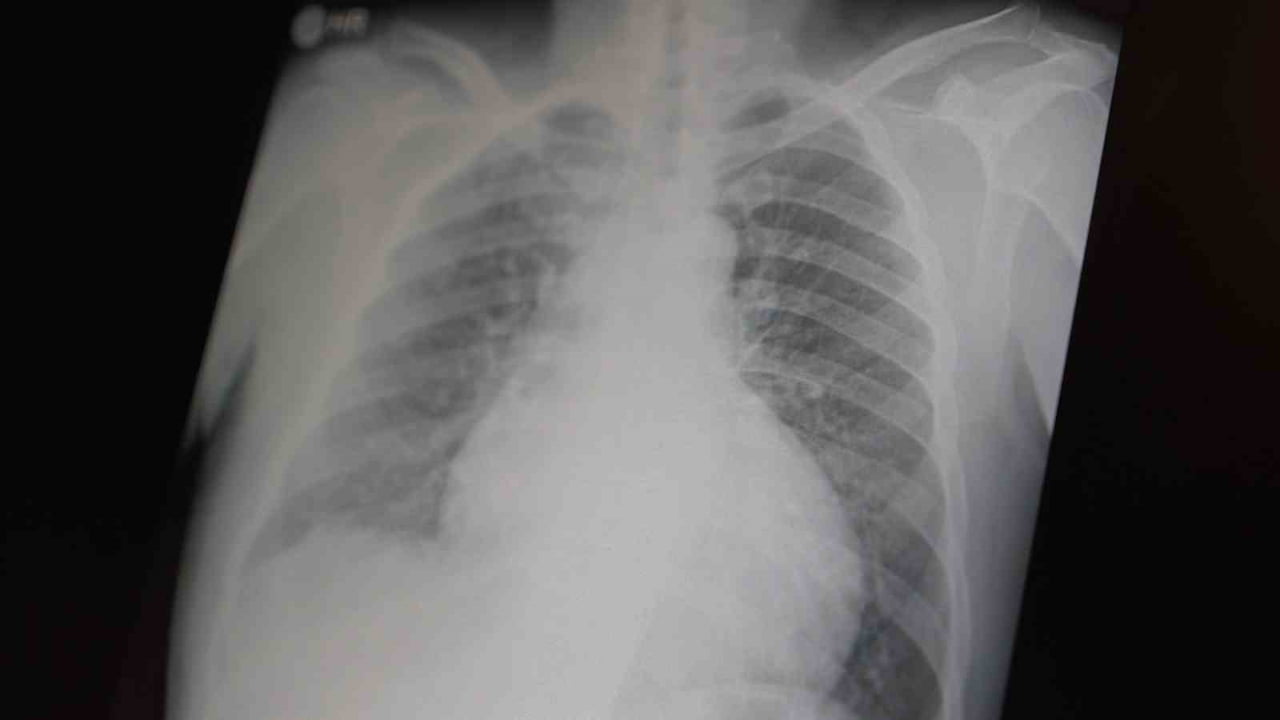

Göğüs Hastalıkları Uzm. Prof. Dr. Şevket Özkaya, tüm dünyada çocuk ve gençleri etkileyen iki önemli bağımlılığın metamfetamin ve kokain olduğunu belirterek, her iki uyuşturucunun ciddi sağlık sorunlarına ve ölümlere yol açtığını açıkladı.

"Tüm dünyada çocukları ve gençleri etkileyen iki önemli bağımlılıktan bahsetmek istiyorum. Bunlar metamfetamin ve kokain bağımlılığıdır. Metamfetamin en ölümcül, en çok bağımlılık yapan, okul çağında en kolay ulaşılabilen bir sentetik uyuşturucudur. Kullanıma bağlı ciddi akciğer ve karaciğer sorunları ortaya çıkıyor. Çok küçük dozlarda bile anında bağımlılık yapabiliyor ve tedaviyle bırakılması çok zor bir bağımlılıktır" dedi.

Açıklamalarında, her iki uyuşturucunun beyin hasarı oluşturduğunu ve nöro sinir hücrelerini harap ederek solunum ve kalbin durmasına sebep olduğunu vurgulayan Özkaya, "Metamfetamin tüm dünyada bir sorun olmanın ötesinde, ülkemizde de gençlerimizi etkileyen toplumsal bir sorun olarak görülmelidir" ifadelerini kullandı.